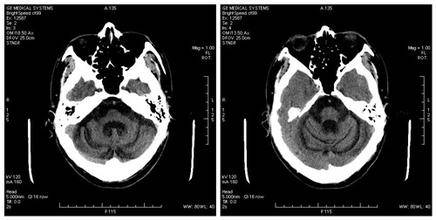

誘因小腦萎縮的原因:

1、外傷性:為腦外傷的后遺癥。按損傷的性質(zhì)又分為閉合性和開放性兩種。開放性又分為穿通性和非穿通性。穿通性又分為火器性和非火器性。是常見引起小腦萎縮的原因。

2、腦梗塞:無論缺血性或出血性腦梗塞,其后期均可發(fā)生,嚴(yán)重的可形成軟化灶等。多發(fā)性、腔隙性腦梗塞發(fā)展為局限性小腦萎縮的人數(shù)雖然不多,但是大多數(shù)患者可導(dǎo)致癡呆。

3、腦出血:經(jīng)治療后有或沒有局限性小腦萎縮,而大多有智能減退,少數(shù)可形成軟化灶,或癡呆。

4、腦鈣化:病人常同時(shí)伴有同側(cè)面部血管痣。全腦彌漫性鈣化可成為導(dǎo)致局限性小腦萎縮的原因。

5、大腦半球萎縮:胎兒期或新生兒期血管阻塞引起的大塊腦梗塞或發(fā)育不全所致。